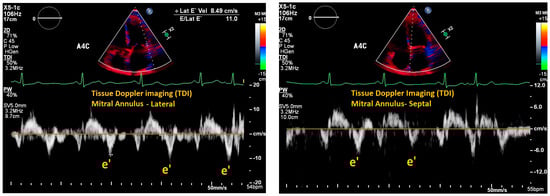

| Mitral E/e’ ratio estimated from the E wave velocity of the mitral inflow Doppler envelope and the tissue Doppler e’ wave velocity at the mitral annulus (septal and/or lateral) | E/e’ ≤ 14 |

|

| |